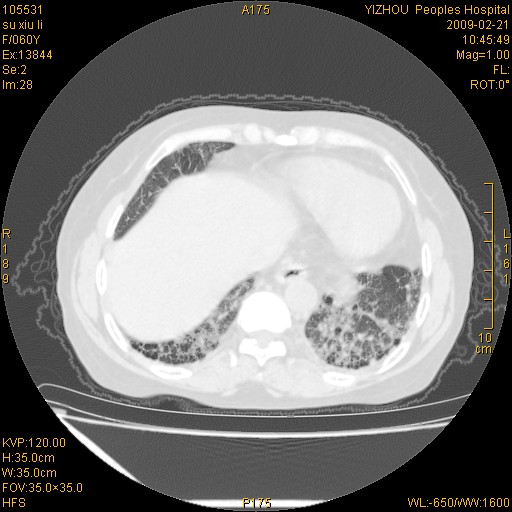

标题: CT18259:两肺间质纤维化? [打印本页]

标题: CT18259:两肺间质纤维化?

女,60岁,反复咳嗽1月。

两肺支扩,以肺为著合并双肺较广范纤维化病变。建议除外结核等病变。

两下肺支扩

符合间质感染,部分纤维化表现

特发性间质纤维化

特发性间质纤维化伴支扩!